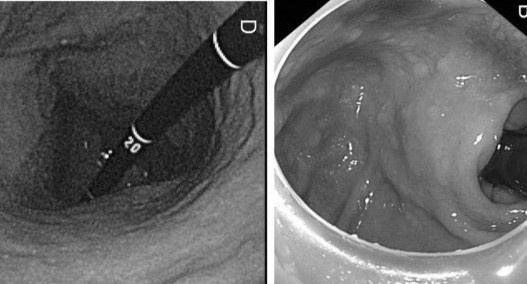

Ngoài sử dụng thuốc điều trị, dưới đây là một số lưu ý bạn nên làm tại nhà khi bị trĩ để cải thiện tình trạng, giảm triệu chứng nhanh.